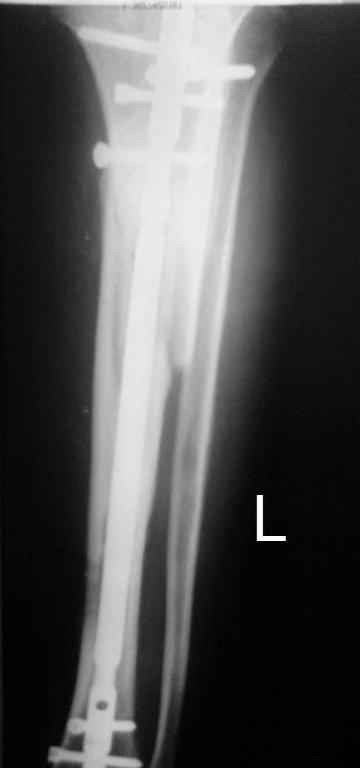

Тогда можно рассмотреть вопрос одновременного удаления штифта, мышечной (в данной области применим проксимально отсеченный лоскут камбаловидной мышцы) или микрохирургической (что более надежно) пластики дефекта мягких тканей, остеотомии проксимального фрагмента большеберцовой кости, остеосинтеза блокируемым штифтом с а/б покрытием, наложения простого аппарата Илизарова (можно из полуколец) для дистракции на штифте. При данном варианте пациент сохраняет возможность полной опоры на ногу, что очень важно для заживления у пожилого пациента) и отпадает необходимость в проведении дополнительный операций (при благоприятном развитии событий).

Выкладываю картинки похожей пациентки. Извините, что без окончательных снимков (сейчас их нет под рукой). Правда мы имели проблемы у данной больной после снятия аппарата, когда промежуточный фрагмент большеберцовой кости сместился на 1,5 см дистально и отошел от проксимальной части кости. До сих пор у пациентки на снимках определяется лишь тонкая полоска кости по задней поверхности за штифтом (образовалось что-то вроде маленького регенерата)в области стыковки промежуточного и проксимального фрагментов. Больная пока решила подождать. Не хочет оперироваться, так как ходит не хромая, работает.

Сейчас в аппарате вытянул около 6 см в верхней трети.